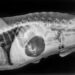

Καλό τότε θα ήταν να επισκεφτείτε τον κτηνίατρό σας. Ένας σωστός έλεγχος για τυχόν προβλήματα υγείας που συνδέονται με την ενοχλητική αυτή συνήθεια δεν βλάπτει.